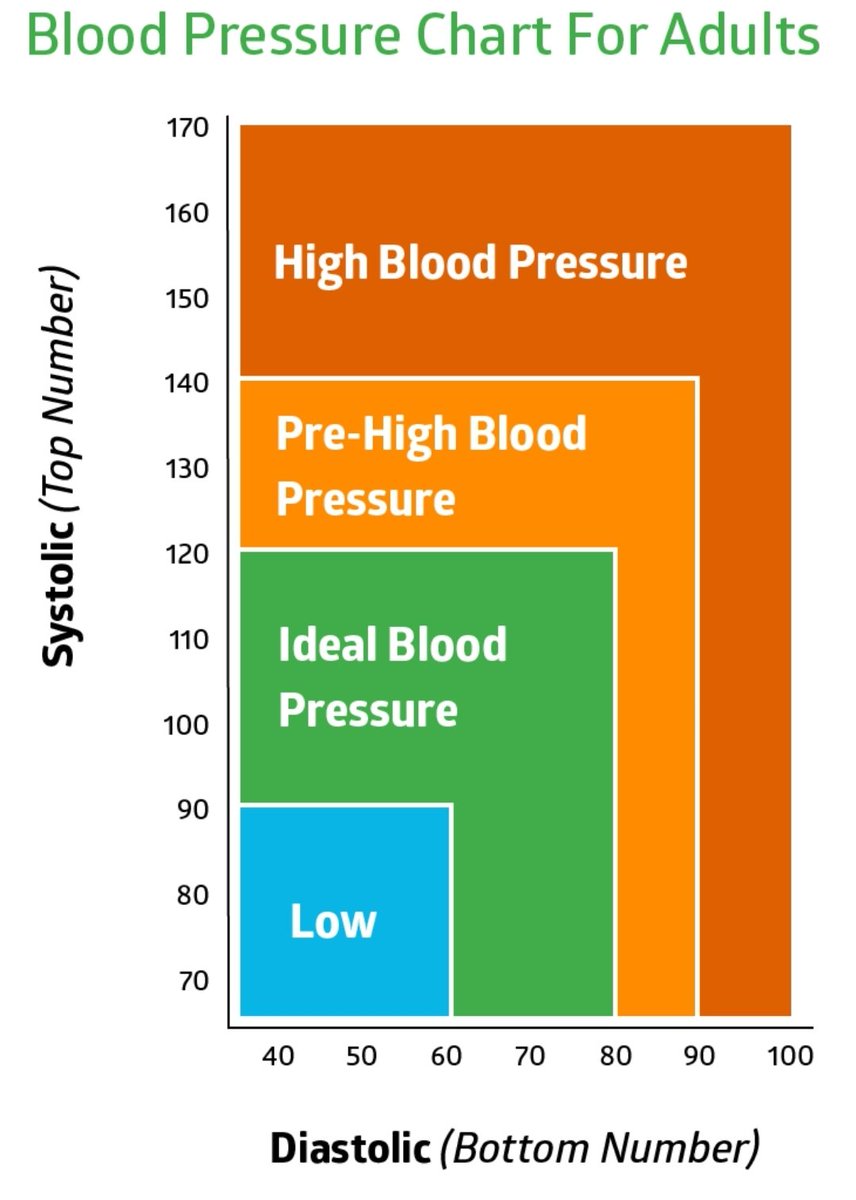

🧠ارتفاع ضغط الدم بشكل مفاجئ

🧠ارتفاع ضغط الدم بشكل مفاجئ

💥السيطرة ع #ضغط_الدم

💥السيطرة ع #ضغط_الدم

🧠ارتفاع الضغط

🧠ارتفاع الضغط